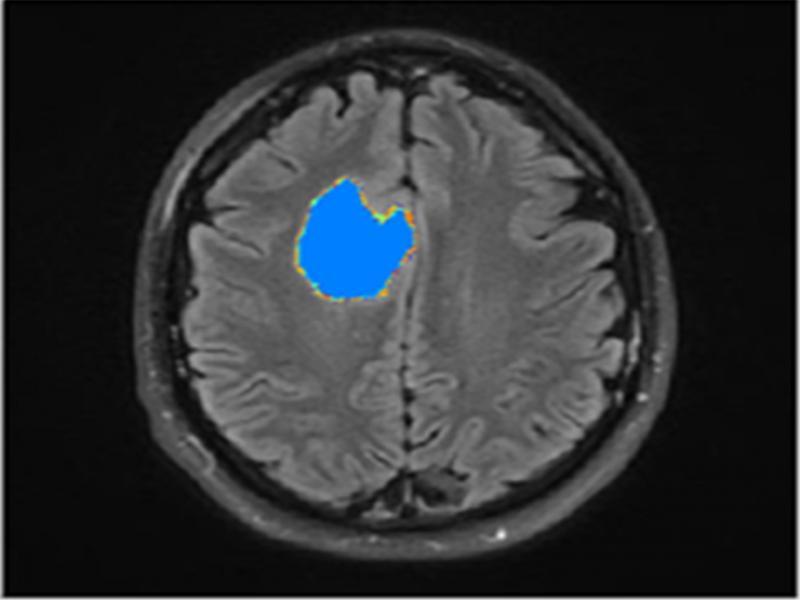

Maximally stable extremal regions (MSER): MSER function fine-tunes the similar intensity pixels by grouping them according to intensity bands. This method is used for blob detection and connects areas of similar intensity. Thus, the detected tumor region is obtained and highlighted for better visualization (Figure 7).

Figure 7:

Post-processing (A) Image with four different coloured clusters superimposed after K-Means clustering and (B) Image after MSER detection.

The outcome of the proposed methodology is seen in figure 9. Figure 8 represents the input image and figure 9 is the processed image with the highlighted tumor region.

Figure 9:

Output image.

A distinct highlighted tumor region is visible in the final output image.